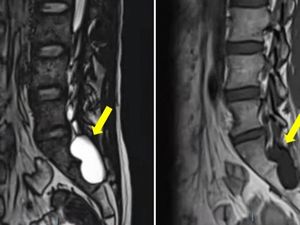

Megan punya keluhan pada tubuhnya, tapi ia ogah periksa. Megan telah salah mendiagnosis kesehatannya sendiri, sampai kista berukuran bayi ada di perutnya.